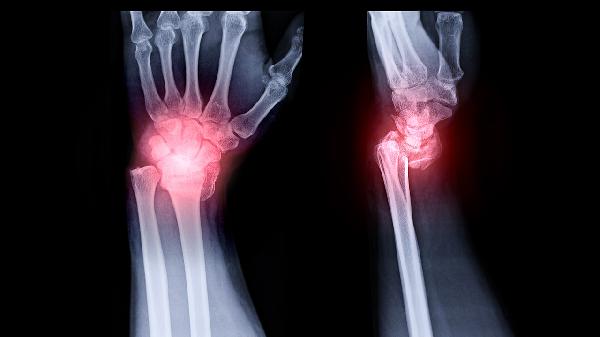

脛骨結(jié)節(jié)骨骺炎可能是生長發(fā)育快、運(yùn)動(dòng)量大、局部血液循環(huán)障礙、遺傳因素、骨骼先天畸形等原因引起,可以遵醫(yī)囑通過一般治療、藥物治療、手術(shù)治療等。